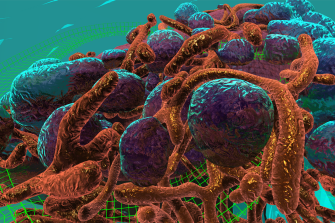

Interactive cell exploration

In 2016, an interactive virtual reality cell environment, the first of its kind, was generated at the 3D Visualisation Aesthetics Lab. The prototype uses the latest room-scale virtual reality technology and high-resolution electron microscopy data to allow researchers to observe the processes by which nanoparticles carrying cancer therapies are internalised and trafficked within a cancer cell. It is anticipated that this work will shift the paradigm of education while accelerating the science discovery process by offering researchers novel perspectives on drug delivery. Initial assessment of the learning outcomes of immersive media education compared with traditional screen-based methods in undergraduate students suggests VR can improve learning but further work is needed.

Watch a video flythrough of the VR cell environment

Educational animation

Based on ground-breaking research being undertaken by scientific collaborators at the Monash Institute of Pharmaceutical Science (MIPS) and the University of Queensland (UQ), the 3DVAL developed a thought-provoking computer-generated animation describing the stages of novel nanoparticle drug delivery to cancer cells isolated in the laboratory. The sequence incorporates accurate high-resolution microscopy data of a breast cancer cell and structural data from the Protein Data Bank to enhance scientific authenticity.

Design-led visualisation of nanomedicines in virtual reality

This research explores how VR can be used as a platform to understand and interact with pre-clinical imaging data – specifically PET-CT- in an immersive and intuitive manner. This interdisciplinary research work is being carried out between the 3D Visualisation Aesthetics Lab (3DVAL) at UNSW Sydney and the Australian Institute for Bioengineering and Nanotechnology/Centre for Advanced Imaging at The University of Queensland, Australia. The project focuses on how carefully-considered aesthetic and design choices such as colour, environment, sound and interface features, can enhance the user experience and comprehension of the 3D data sets.

Read more about design-led 3D visualisation of nanomedicines in VR

Collaborators: Prof Kris Thurecht, Dr Zach Houston, Dr Nick Fletcher (University of Queensland)

Funded by the ARC Centre of Excellence in Convergent Bio-Nano Science & Technology (CBNS)